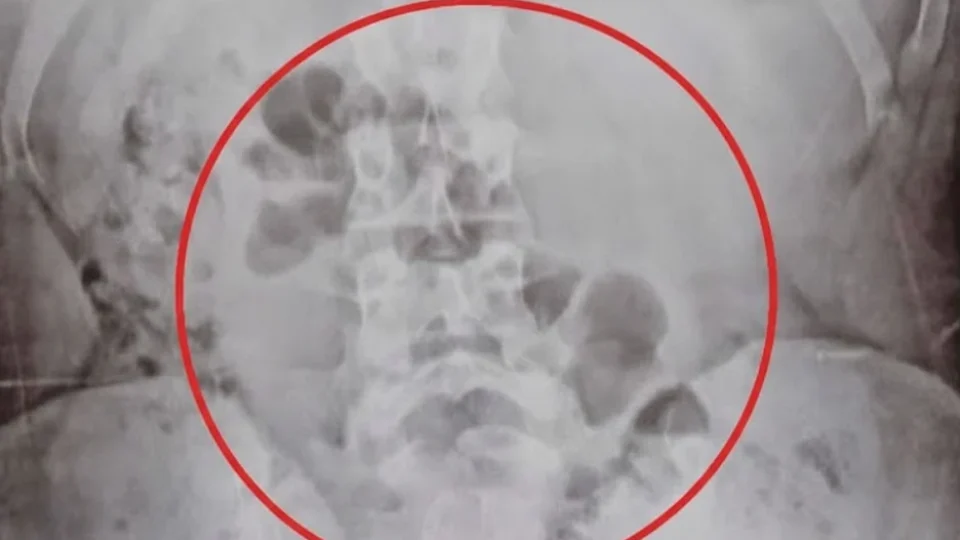

A mulher foi levada para atendimento médico, onde exames constataram que diversas porções de drogas estavam dentro de seu estômago. As substâncias foram apreendidas após os procedimentos de saúde, e a suspeita permaneceu sob custódia para responder pela situação.